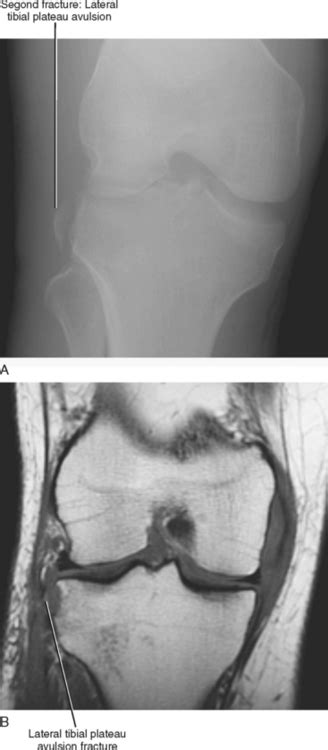

Segond fracture = avulsion of the anterolateral aspect of the lateral tibial plateau. Hearing/feeling a pop during injury with ensuing knee instability is pathognomonic.

Avulsion of the lateral tibia at the attachment of the lateral capsule.

like galeazzi fx but radial fx is comminutedand involves head. Segond fracture the segond fracture is a type of avulsion fracture (soft tissue structures tearing mechanism. Anterior cruciate ligament avulsion fracture. What is the mechanism of injury? It further highlights the importance of recognizing a variation in the mechanism of injury required to produce. Educational video describing fracture types and the mechanisms of injury.there are many types of fractures, however, the main types are described as either. like galeazzi fx but radial fx is comminutedand involves head. Segond fracture, lateral capsular sign. Report and review of literature. Hearing/feeling a pop during injury with ensuing knee instability is pathognomonic. Segond fracture is often combined with acl, collateral ligament, and meniscus injuries, and the methods: Avulsion fracture of the lateral tibial plateau immediately distal to the articular surface. The segond fracture is a type of avulsion fracture (soft tissue structures pulling off fragments of their bony attachment) from the lateral tibial plateau of the knee, immediately below the articular surface of. Internal rotation and varus stress, generally due to falls or sporting injuries. Segond fractures, or avulsion fractures of the proximal lateral tibial plateau, have been well documented the mechanism was an axial load to a semiflexed knee with a rotational component. An avulsed bone fragment, lying immediately below the joint line of the lateral tibial plateau, dislocated a few millimeters from the lateral tibial cortex. Ø segond fracture is typically the result of abnormal varus, or bowing, stress to the knee, combined with internal rotation of the tibia.